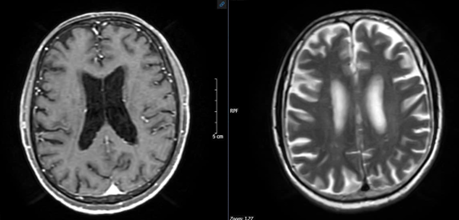

Chụp cắt lớp vi tính lồng ngực: Thùy dưới phổi trái có khối tỷ trọng tổ chức kích thước 30x21mm sau tiêm ngấm thuốc, thượng đòn phải và trung thất có vài hạch, nhóm 2, 4 lớn nhất kích thước 16x17mm, bờ rõ, ngấm thuốc sau tiêm.

Hình 1: Hình ảnh cắt lớp vi tính lồng ngực: Phổi trái có khối tỷ trọng tổ chức kích thước 30x21mm sau tiêm ngấm thuốc (vòng trong màu đỏ)

Nhận xét: Trước điều trị hóa chất thùy dưới phổi trái có khối tỷ trọng ngấm thuốc, thượng đòn phải và trung thất có vài hạch, nhóm 2, 4 bờ rõ, ngấm thuốc sau tiêm, các hạch dọc động mạch chủ bụng ngấm thuốc, tuyến thượng thận trái dày thân tuyến, tuy nhiên sau điều trị hóa chất 3 chu kỳ, không thấy hình ảnh khối tỷ trọng ở phổi, các hạch ở trung thất, thượng đòn, dọc động mạch chủ bụng cũng như hình ảnh dày thận tuyến thượng thận.